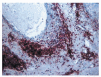

Los casos de mucinosis folicular urticarial fueron los más fácilmente identificables histológicamente. Los depósitos de mucina eran escasos; sin embargo, el infiltrado inflamatorio era muy abundante, siendo su localización superficial y profunda (incluso hasta tejido celular subcutáneo). El dato más característico era la gran abundancia de eosinófilos, significativamente superior a la de todas las otras formas clínicas definidas de mucinosis folicular (fig. 8). Los depósitos de mucina eran escasos.

Fig. 8.--Mucinosis folicular urticarial. Abundantes eosinófilos.

La mucinosis folicular urticarial fue descrita en 1980 por Enjolras et al en 10 pacientes con placas inflamatorias en cara, cuello y tórax, de aparición brusca, que histológicamente se caracterizaban por mucinosis folicular25. Otras publicaciones posteriores parecen confirmar la existencia de esta entidad26, 27. El cuadro se caracteriza por brotes recurrentes, intensamente pruriginosos de placas eritemato-edematosas, que se resuelven a las pocas semanas, recayendo posteriormente. Las recaídas continúan a lo largo de años, sin evolucionar a linfoma cutáneo. En nuestra serie hemos encontrado tres pacientes con esta clínica y todos mostraban características histológicas particulares, destacando la intensidad del infiltrado y la gran abundancia de eosinófilos. Estas particularidades clínicas y patológicas permiten reconocer con facilidad a esta variedad de mucinosis folicular que se da típicamente en varones de edad media (30 años). Pese a que uno de nuestros pacientes mostraba clonalidad en el estudio genético de reordenamiento, ningún caso evolucionó a linfoma.